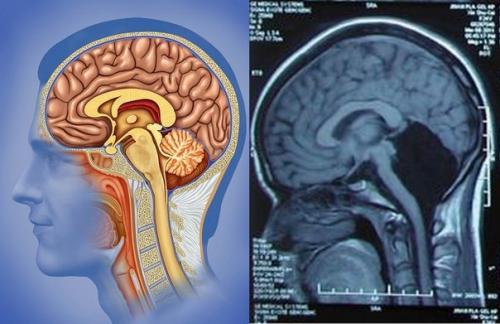

На фото: слева - нормальный мозг, справа - с отсутствующим мозжечком.

Китайские доктора были шокированы, увидев на снимках головного мозга одной из пациенток отсутствующий мозжечок. 24-Летняя девушка обратилась в клинику с жалобами на сильную тошноту и рвоту. Результаты обследования удивили даже опытных специалистов, которые были уверены, что в своей жизни видели всё.

"КТ- и МРТ- Исследования не Выявили Никаких Даже Малейших Остатков Тканей Мозжечка, что Подтверждает его Изначальное и Полное Отсутствие", - написали доктора в своём отчёте для журнала Brain.